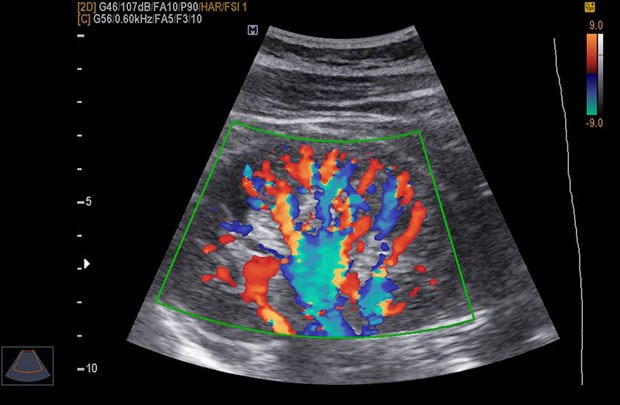

Принцип проведения допплерометрии практически не отличается от принципа проведения обычного УЗИ. В обоих случаях используются датчики с излучением. Правда, в первом его мощность все-таки сильнее, благодаря чему и удается оценить кровоток в маточных артериях, в сосудах плода и плаценты, а также их проходимость и просвет. На основании полученных данных впоследствии врачи смогут судить о развитии крохи и делать прогнозы относительно возможных осложнений беременности.

Интересно, что доплер не показывает пол ребенка и не выводит на монитор его изображение. Он просто сканирует сосудистую систему, его и плаценты, и позволяет удостовериться в том, что будущий малыш получает достаточно кислорода, а его сердце работает как положено.

- дуплексное – с его помощью врач проверяет интенсивность кровотока и делает выводы относительно строения и проходимости сосудов;

- триплексное – показывает все то же самое, только в цветном изображении, благодаря чему специалист может проследить еще и движение эритроцитов и получить более развернутую картину протекания беременности.